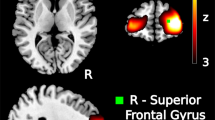

Figure 1 shows a summary of the diagnostic utility of brain SPECT in distinguishing PTSD from TBI. Figure 2 shows two groups of ROC curves. Figure 2a shows ROC curves delineating veterans with PTSD from those with both PTSD and TBI. Figure 2b displays ROC curves distinguishing veterans with TBI from those with PTSD and TBI. Figure 3 shows two rows of volume rendered SPECT images, each from separate subjects. The first volume rendered row shows inferior underside surface rendered images. The second row shows intensity projection images in which white colors represent the top 8 % and red colors represent the top 15 % of cerebral flow in that subject’s brain compared to their whole brain perfusion. A healthy control shows normal higher perfusion to the cerebellum. The PTSD subject shows increased perfusion in the brain – particularly in the frontal lobes. The TBI subject shows decreased perfusion throughout by comparison. The subject with both PTSD and TBI shows perfusion that is intermediate in that it is lower than the person with PTSD but higher than the subject with TBI. These representative images highlight how, in a given set of subjects, there is increased perfusion in PTSD and hypoperfusion in TBI with an intermediate imaging pattern in persons with both.